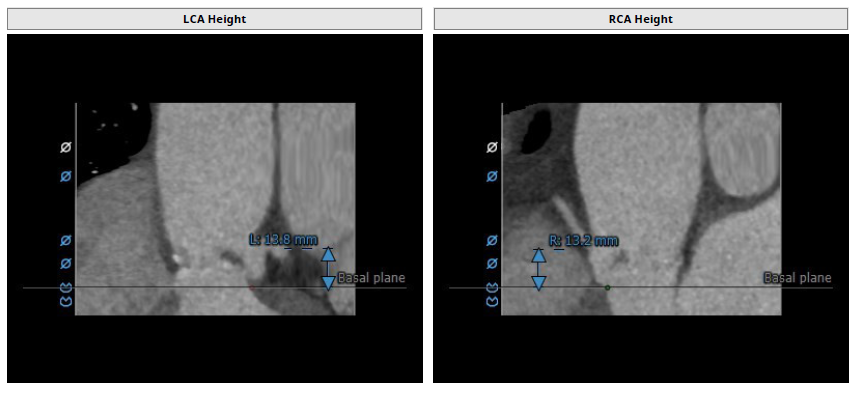

该病例为老年女性,主动脉瓣重度狭窄伴有轻度反流。CT及超声检查提示三叶式主动脉瓣,瓣膜钙化重度钙化,右无冠窦钙化较多,主动脉弓长度可,瓣环角度为57°,左、右冠脉开口高度13mm,但瓣叶增厚绵长,左右冠脉术中均有堵塞风险因此瓣膜选择及释放均需十分谨慎,并预先做双侧冠脉。双侧股动脉直径可,综合评估考虑右股动脉更适宜为主入路。

经过团队严谨的评估及充分的讨论,决定先行23mm球囊充分预扩并进行瓣环测量,并准备TAV26规格的Pro Style预装干瓣可回收TAVR系统。